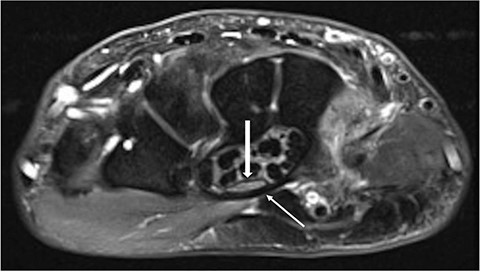

Clinically, the patient was initially diagnosed with a bilateral carpal tunnel syndrome confirmed by electromyogram (EMG)/nerve conduction velocity (NCV) (Fig. 1), which was treated surgically in the typical manner and led to freedom from symptoms. Over the further course, diffuse pain occurred in both legs, and the pain-free walking distance decreased over time. Colour coded duplex sonography (CCDS) did not reveal any evidence of peripheral arterial occlusive disease. Diabetes mellitus could be excluded by laboratory tests. In the imaging diagnostics carried out by means of magnetic resonance imaging (MRI) of the axial skeleton, an absolute spinal canal stenosis at the level of vertebral bodies L4–L5 due to a marked hypertrophy of the ligamenta flava with additional deforming spondylosis could be confirmed (Fig. 2).

MRI of the lumbar spine. Left sagittal slice with a stenosis of vertebral bodies L4/L5, in the axial slice (centre) corresponding stenosis (long arrow) with clear thickening of the ligamenta flava (short arrow). On the right, there is a clear cerebrospinal fluid blockage in the area of the stenosis.